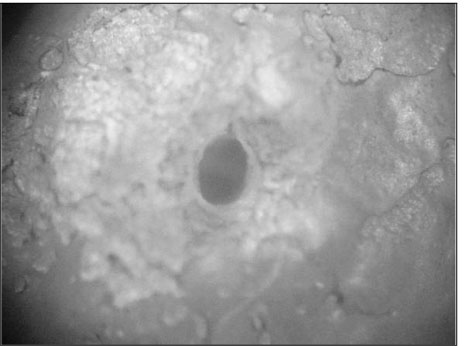

Figure 4

Photograph of section with no isthmus (×40)

Figure 4 Photograph of section with no isthmus (×40)